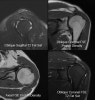

어깨 관절의 MRI 표준판독지

1. Joint effusion : None

2. Rotator cuff : Tendons intact without evidence of tendinopathy or tears; normal muscles without evidence of atrophy, edema, or other abrnomalites.

3. Long head of biceps tendon : Normal in position, size, and signal

4. Glenoid labrum : No tear, detachment, or other abnormalities shown; no paralabral cyst

5. Subacromial/subdeltoid bursa : Nomral without evidence for bursitis

6. Acromioclavicular and glenohumeral joints : No osteoarthritis or other abnormalities

7. Osseous structures : Normal

8. Other abnormalities : None

* Opinion : Normal MRI of the (right/left) shoulder